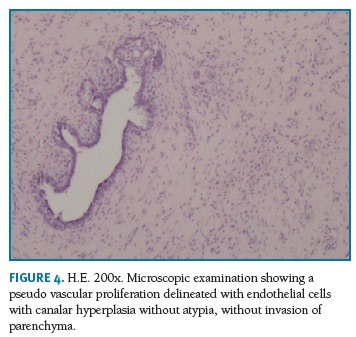

Definitive pathologic diagnosis of Pseudoangiomatous Stromal Hyperplasia (Fig. 4-5-6-7-8) was made on surgical specimen of mastectomy. The patient had regular follow-up at our department. Last visit was in May 2018, and no signs recurrence or contralateral breast cancer were diagnosed in those 11 years of follow-up.